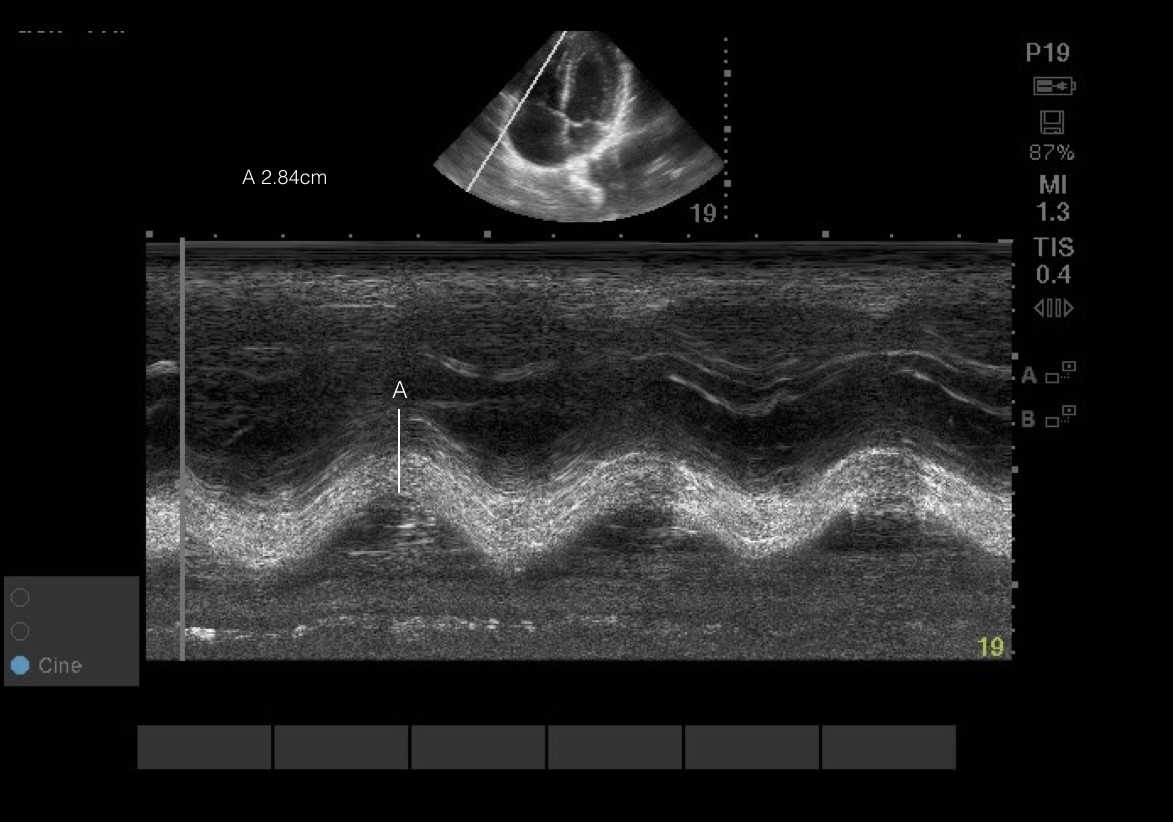

画像6、7 & 動画1 TAPSE:RVは主に頂点から底辺までの縦方向に収縮します。 そのため,プローブに向かったり離れたりする横方向の自由な動き(TAPSE)と,この収縮の強さ(S’)を評価することで,RVの収縮機能の代理的なマーカーとして働くことができる。 実行するには、三尖弁の高さでMモードカーソルを側方自由壁に当て、sin波を得る。 ピークからバレーまで、あるいは収縮期および拡張期の最大のエクスカーションを測定する。 TAPSEの異常<16mm。 S’の場合:脈波ドップラーを外側環状動脈のすぐ遠位にある外側自由壁の上に置く。 ベースラインからの最大速度を測定する。 S’の異常 < 9.5cm/s

Pitfalls: TAPSEとS’は角度に依存する。 そのため、質の悪いA4CビューではRV機能を評価する能力が著しく低下する。 さらに、これらの代替マーカーは一平面上でしかRVを評価しないため、TAPSE/S’が正常であってもRVに重大な機能障害がある場合がある。 これらの限界にもかかわらず、TAPSE/S’は肺高血圧症患者のRV機能不全の病的状態と相関している。